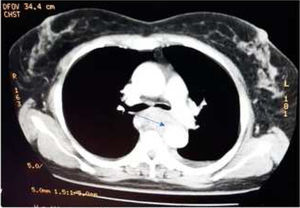

Caso clínicoPaciente femenino de 58 años, procedente de Supatá, Cundinamarca, ama de casa, sin antecedentes patológicos ni quirúrgicos de relevancia. Ingresó al hospital de tercer nivel por un cuadro de 6 días de evolución de disfagia secundaria a ingesta de cuerpo extraño (espina de pescado). En esa institución realizan una endoscopia de vías digestivas altas, que evidencia un cuerpo extraño a 25cm de la arcada dentaria, y realizan manejo mediante avance de este hasta cámara gástrica con posterior egreso hospitalario. Reingresa por episodio de dolor toracoabdominal, elevación de las cifras tensionales, hematemesis y melenas. Realizan toma de hemograma, donde se evidencia leucocitosis y anemia severa con requerimiento de transfusión de 2UI de glóbulos rojos; toman TAC de tórax, que mostró colección mediastinal en el tercio medial y distal esofágico con colección de aproximadamente 2cm con imagen de gas en su interior, compatible con absceso, además de alteración del contorno aórtico a la altura de la carina, sospechosa de lesión del espacio intramural o hematoma localizado (figs. 1 y 2), por lo que consideran perforación con lesión de aorta adyacente y remiten a nuestra institución para manejo por Cirugía Cardiovascular.